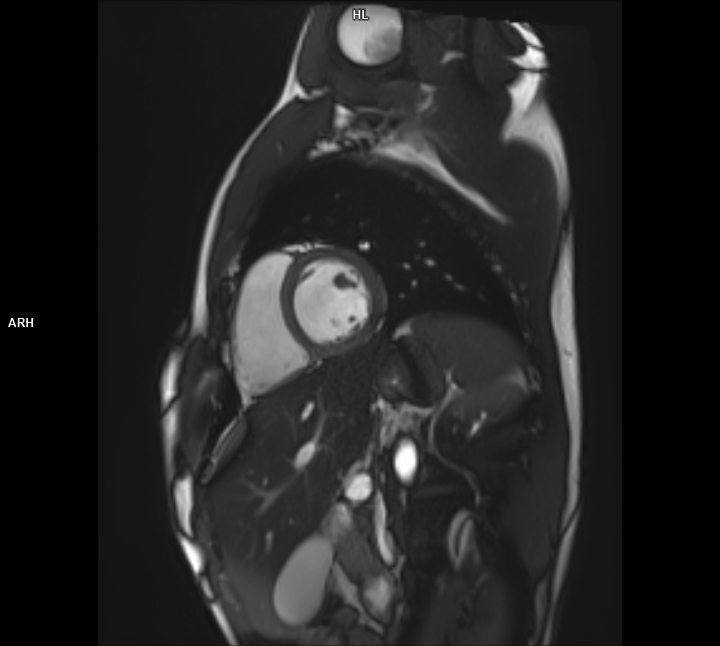

• 3 TESLA MR ÇEKİM GÖRÜNTÜLERİ

3 Tesla MR Çekim Görüntüleri

• 3 Tesla MR Çekim Görüntüleri